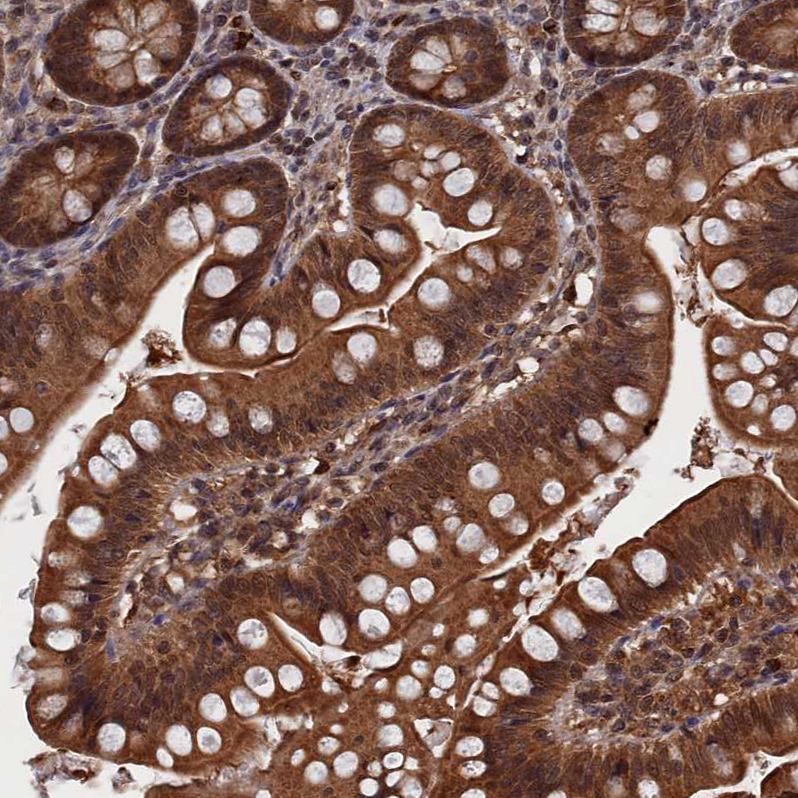

Immunohistochemical staining of human cerebral cortex shows strong cytoplasmic positivity in neurons.